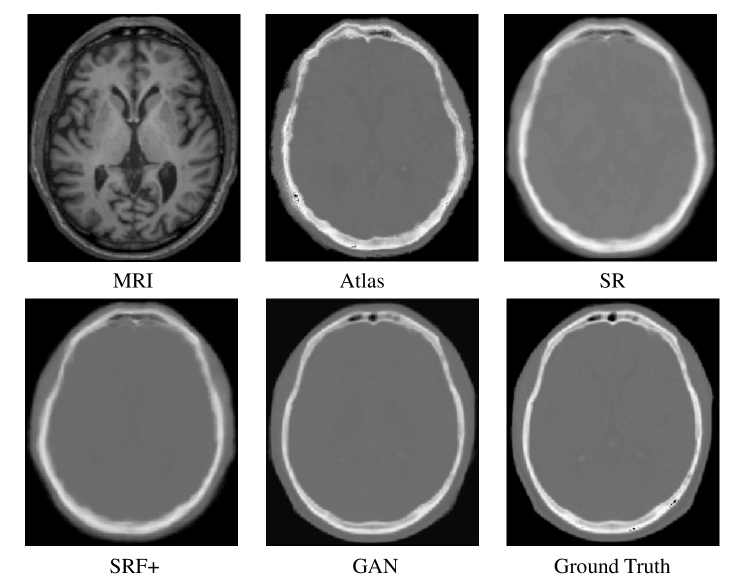

To qualitatively compare the estimated CT by different methods, we visualize the generated CT with the ground truth in Fig. 6. We can see that the proposed algorithm can better preserve the continuity, coalition and smoothness in the prediction results, since it uses image gradient difference constraints in the image patch as discussed in Section  2.1. Furthermore, the generated CT looks closer to the real CT compared to all others, and we argue that this is due to the adversarial training strategy which constrains the generated images to be so similar to the real ones that a even a complex discriminator cannot perform better than chance.

Refer to caption

Figure 6: Visual comparison of original MR images, the estimated CT images by our method and other methods, and the ground-truth CT images on 1 typical subject on the brain dataset

We also quantitatively compare the predicted results in Table  1 in terms of PSNR and MAE. Our proposed method outperforms all other methods in both metrics, and it further demonstrates the advantage of our architecture.